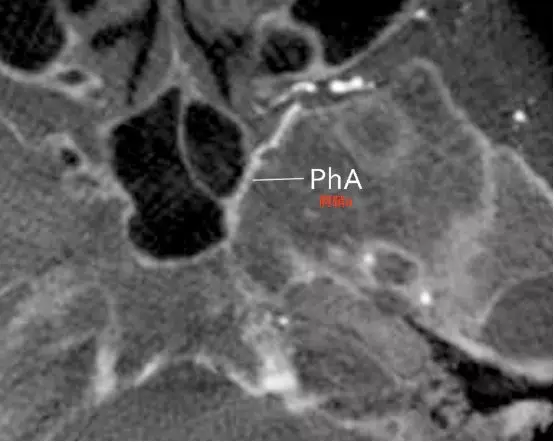

Tanoue等报道了一例颈内动脉近端闭塞,左侧颈外动脉CTA水平位重建,可观察到翼管动脉、圆孔动脉和腭鞘动脉等(Tanoue 2013)。

b,腭鞘动脉,又称咽动脉(pharyngeal artery)发出紧邻翼管动脉,向后下方走行,与翼腭神经伴行,通过腭鞘管(咽管)(Tanoue 2013)。

圆孔动脉向后上走行,与上颌神经伴行,进入圆孔(Tanoue 2013)。圆孔位于翼管上方。